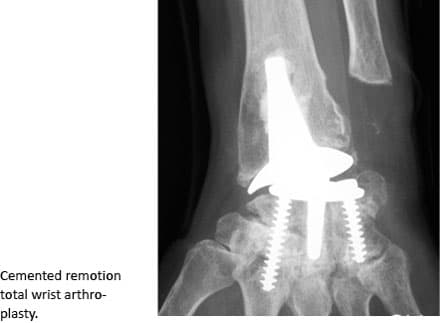

In Group 1, we included consecutive patients operated with a third generation TWA at Gentofte Hospital or at Rigshospitalet, Denmark, during the 1999-2013 period. We evaluated the patients with the DASH or QuickDASH questionnaires: eight Universal (Integra Life Sciences Corp., Plainsboro, NJ, USA) and 96 Remotion (SBI Inc., Morrisville, PA, USA). Two patients were excluded because they did not attend the 12-month follow-up examination. This group (102 patients) was used for the assessment of the construct validity, internal consistency, floor/ceiling effects and responsiveness of the QuickDASH (Figure 1).